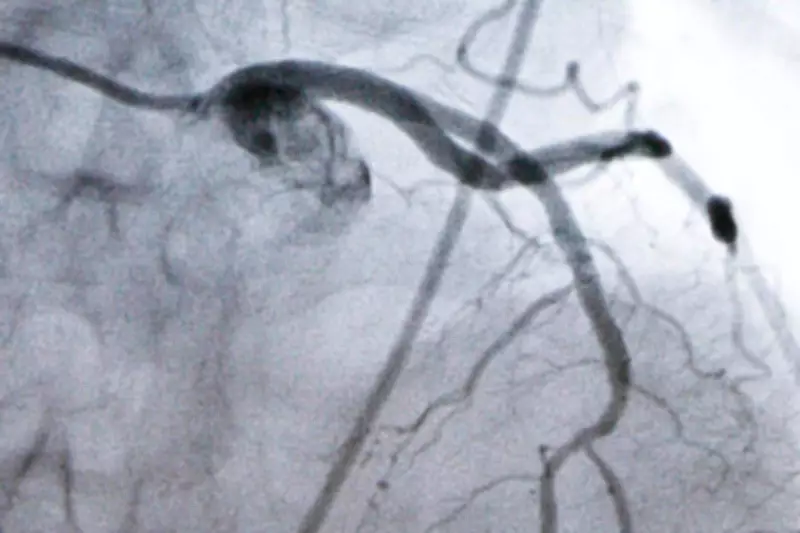

The experimental medication is designed to target cholesterol levels through a novel mechanism, potentially offering advantages over existing therapies such as statins. Early studies suggest it could help reduce low-density lipoprotein (LDL) cholesterol, often referred to as "bad" cholesterol, which is a major contributor to plaque buildup in arteries and increased risk of heart attacks and strokes.